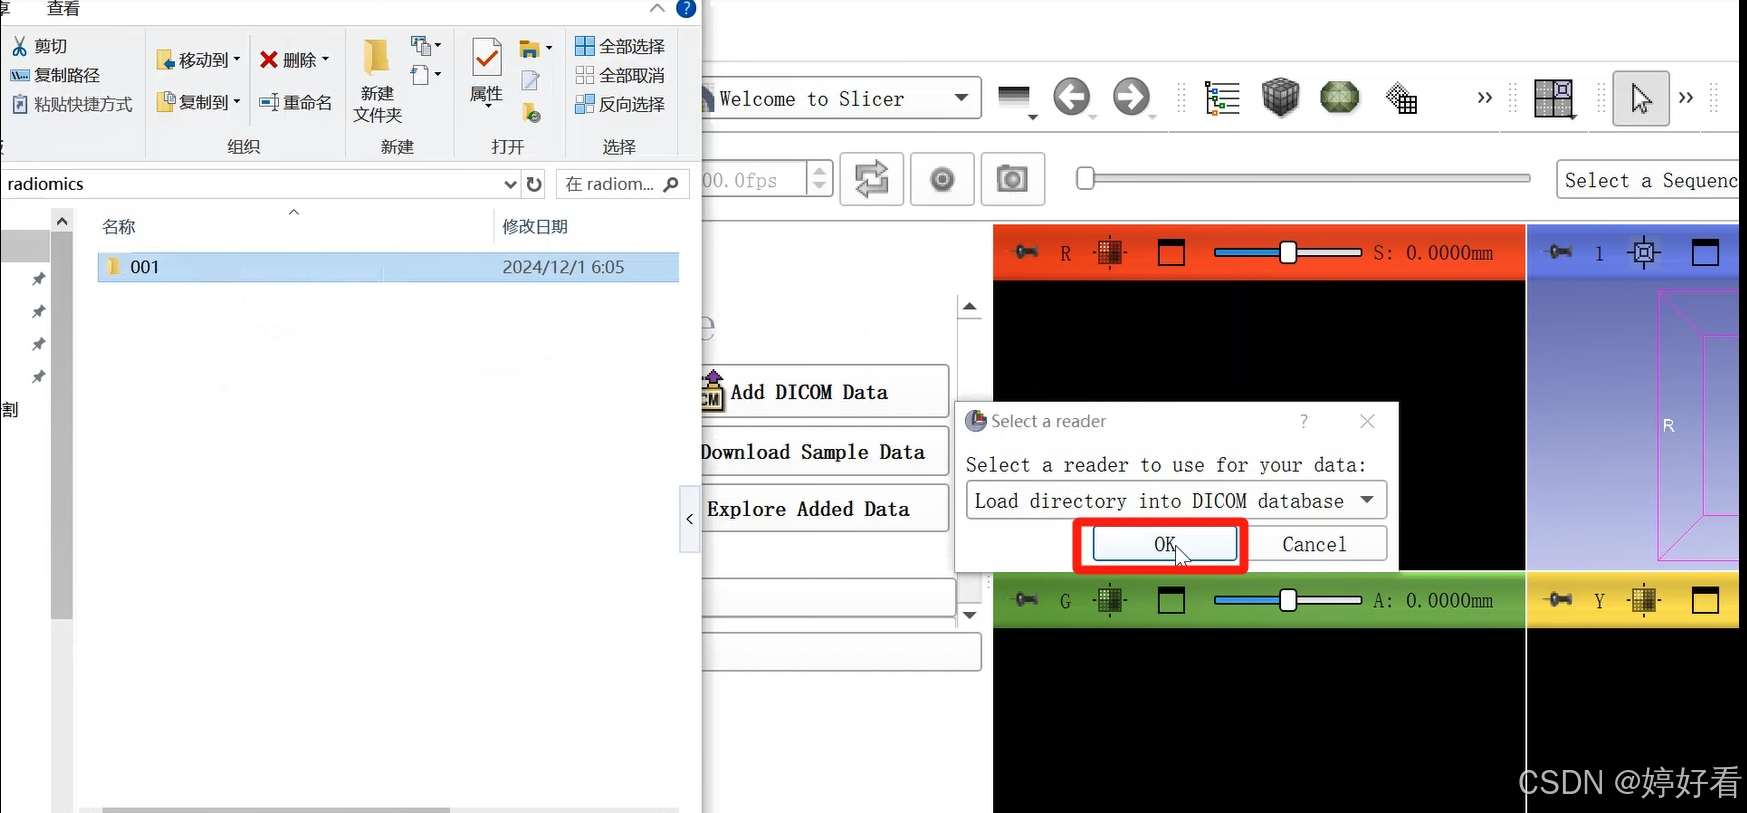

1.1 首先,把包含DICOM格式影像图片的文件夹直接拖到3D slicer的界面,然后点击OK。